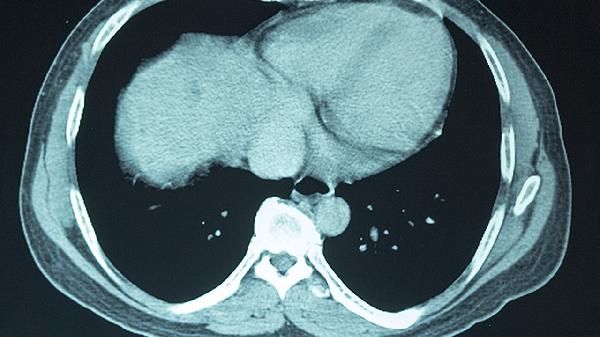

日常生活中,大脑供血不足的患者应定期监测血压、血糖和血脂,定期做颈部血管超声或头颈部CTA检查以了解血管状况。避免突然改变体位,预防跌倒。保持情绪平稳,避免剧烈运动和重体力劳动。一旦发现症状加重或出现新的神经功能问题,应及时就医。在饮食上,可以适当吃一些深海鱼、坚果等富含不饱和脂肪酸的食物,有助于保护血管健康。